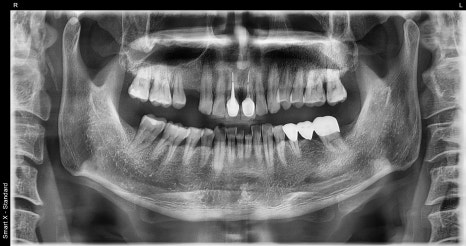

🖼️ 치료 전 사진

왼쪽 사진: 치료 전 전체 엑스레이(파노라마 사진)입니다.

오른 사진: 신경치료 전, 기존 크라운(씌운 치아)을 제거하고 촬영한 부분 엑스레이입니다.

➡ 오래된 보철물 안쪽으로 충치가 깊게 생겨, 신경치료가 꼭 필요한 상태였습니다.

➡ 통증과 불편감이 있었고, 신경치료와 함께 앞쪽 빠진 치아 부위는 임플란트를 통해 기능 회복도 함께 진행했습니다.